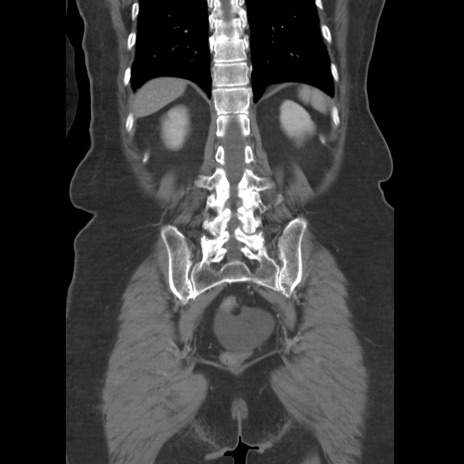

症例19(冠状断像)

【症例】80歳代女性

【主訴】下腹部痛

【現病歴】約8時間前より下腹部痛の出現あり、救急外来受診。

【既往歴】両側付属器切除

【身体所見】意識清明、下腹部正中に手術痕あり、その部位に一致して圧痛と反跳痛あり。腸蠕動音は亢進。

【データ】WBC 9300、CRP 0.15